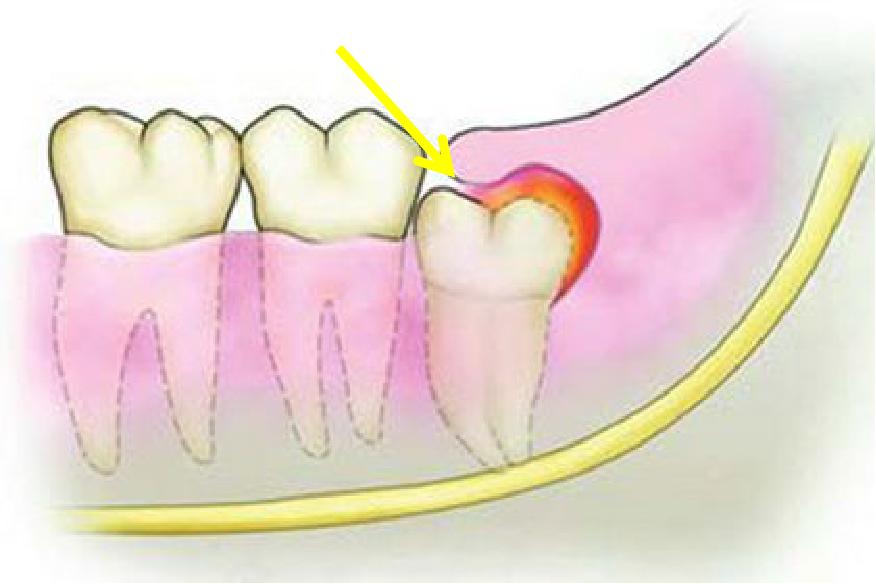

萌出之初,牙冠和牙肉之间形成空隙。上颌因为智齿靠近软腭,刷牙易引起恶心,下颌智齿靠下颌骨的前方,空间有限,牙刷刷头较难深入,清洁不到位,食物残留,细菌聚集,引发感染,称智齿管周炎。